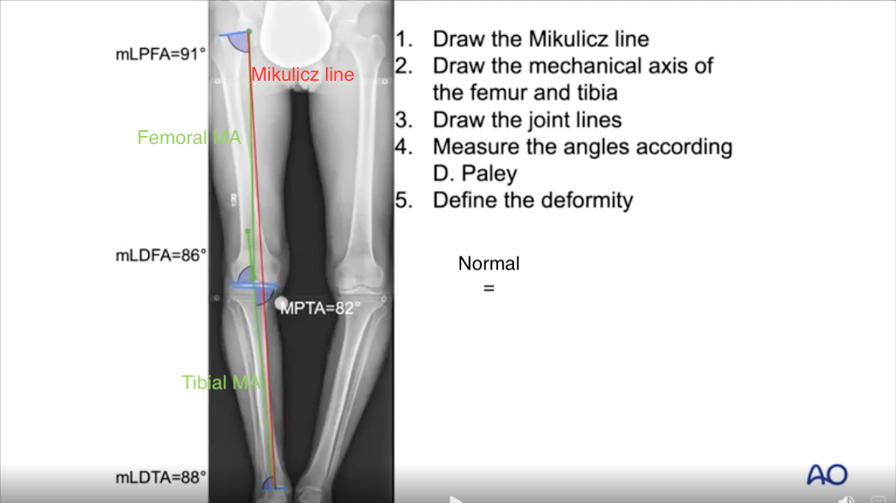

Analyzing the deformity in the frontal plane allows a check of where the limb’s mechanical axis (MA) crosses through the knee joint. Also called the Mikulicz line, this axis extends from the center of the hip to the center of the ankle. If it does not also pass through the appropriate part of the knee joint, i.e., slightly valgus, the knee is malaligned.

Using a frontal plane view, the relevant angles are measured following Dror Paley’s technique. Rather than using the Mikulicz line, Paley used two separate lines, one running down from the middle of the hip to the target MA/joint-line intersection, and one running up from the middle of the ankle through the same point. With these in place, the angles of the hip, the knee (femur and tibia) and the ankle can all be determined, as well as the mechanical tibiofemoral angle (mTFA) (normally 0-2 degrees). And finally there’s the joint line convergance angle (JLCA), i.e., the angle across the joint between the distal femoral and proximal tibial surfaces. Like the mTFA, the JLCA is normally 0– 2 degrees. A knee with a JLCA greater than 2 degrees is varus; one with a negative JLCA is valgus.

Based on that standard long x-ray, planning an osteotomy has five main steps:

- Define the malalignment

- Locate the deformity

- Define the target alignment axis

- Decide which osteotomy is required and location of hinge point

- Measure the correction angle with the Miniaci method

1. Defining the malalignment

To define the malalignment, a Mikulicz line must be drawn, i.e., from the center of the femoral head to the center of the ankle. If that line crosses the knee joint medially of the normal range, the alignment is varus. If the deviation is greater than 15mm, it is considered obvious varus. If it crosses laterally of that range, the alignment is valgus. The threshold for an obvious valgus malalignment is 10mm. The designation of obvious is an important indicator for osteotomy correction.

2. Locating the deformity

As noted earlier, the deformity can be located by drawing the mechanical axes and joint lines, measuring the relevant angles and comparing the results with normal values. Where intraarticular deformity is also present, this will normally self-correct when the bones are realigned. Therefore, we need to remember to subtract the predicted changes in the lateral and medial joint gaps from the overall correction.